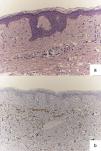

El estudio histológico en todas las biopsias realizadas mostró un infiltrado dérmico de células anaplásicas dispuestas en hilera (fig. 3a) positivo para la tinción de GCDFP-15 (fig. 3b). Asimismo, mostró positividad débil para receptores de estrógenos y progesterona, her2 negativo y un índice de proliferación Ki67 del 20%, por lo que se introdujo un nuevo ciclo quimioterápico con capecitabina 2g/día, a pesar del cual la paciente falleció a los 2 meses de iniciarlo.